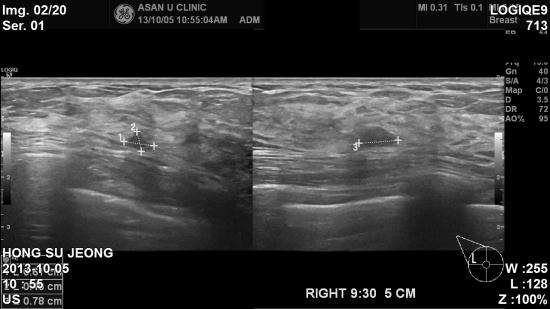

초음파 검사결과 우측유방에 0.78 cm 의 혹이있어

조직검사 시행하였고,

유관상피내암으로

진단되셨습니다